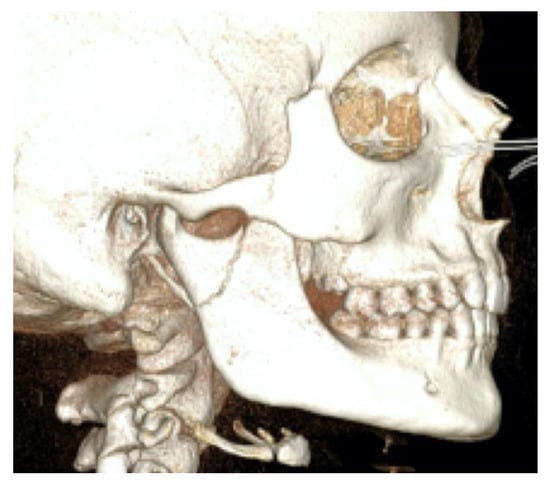

The second patient was a male, aged 20, with a right condylar diacapitular fracture (Figure 4). The patient also presented a coronal fracture of the element 43 due to the trauma. The other teeth were sound, but the 37 was unerupted. He presented a slight class III malocclusion and a posterior open bite on the left. In this case, there was the need to not exert force on the fractured tooth, and to balance the traction points of the rubber bands despite the absence of the 37, avoiding extrusive forces on the 27.

Figure 4. Patient 2, male, aged 20, with a right condylar diacapitular fracture.